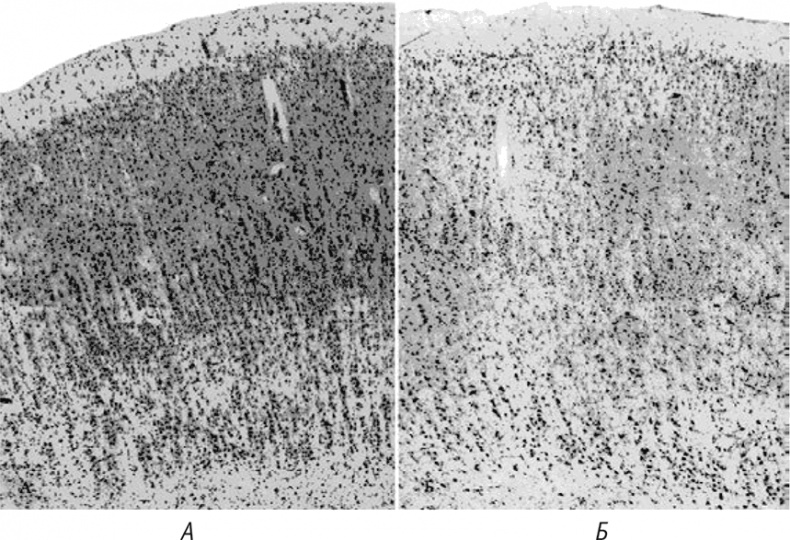

Изменения в мозговой ткани, напоминающие основные признаки изменений при куру и болезни Крейтцфельдта – Якоба, были выявлены и в мозге людей, страдающих болезнью Альцгеймера, старческим слабоумием, и даже… у внешне здоровых старых людей! Конечно, у последних эти изменения не носили столь ярко выраженного характера, как при прионных болезнях, однако гибель нейронов и размножение клеток глии в мозговой ткани стариков имели место (рис. 21). Кроме того, электронная микроскопия и биохимический анализ амилоидных бляшек при куру и в нормально стареющем организме человека подтвердили их сходство.

Иллюстрация к книге — Многоликий вирус. Тайны скрытых инфекций [i_040.jpg]

Рис. 21. Гистологические срезы мозга людей разного возраста: А – 24 года; Б – 76 лет. Вид на бо́льшая разреженность нейронов на фрагменте Б